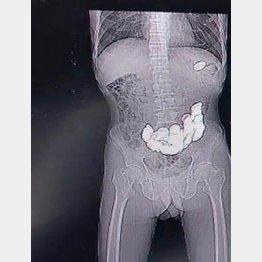

精神疾患のあるインド人男性が緊急手術!「187枚のコインをのみ込んじゃいました」

インド南西部カルナータカ州に住む58歳の男性が先週末、胃痛を訴えて病院に駆け込んできた。吐き気もあり、何とかしてほしいという。

医師がX線検査と内視鏡検査をすると、大量のコインが胃の中にあることが判明し、関係者は仰天! その日のうちに外科手術を行って胃の中からコインを摘…